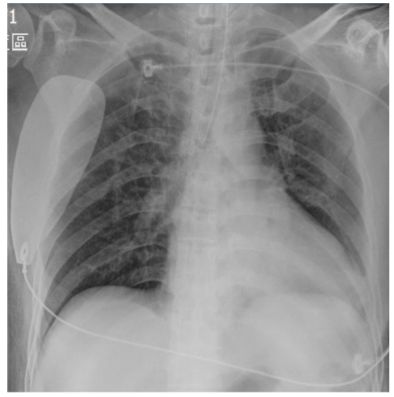

20. 一位65歲男性,有高血壓,糖尿病與B型肝炎合併肝硬 化病史.此次就診之主訴為靜止時喘不過氣來,且有端 坐呼吸與下肢水腫.過去4個月有乾咳,體重減輕5公斤 與倦怠感.體溫為攝氏37度,心跳為規則心律,每分鐘78 跳,呼吸為每分鐘17次.血壓為158/95毫米汞柱.胸部X 光呈現心臟擴大,胸部電腦斷層掃描呈現大量心包膜 積液.心包膜穿刺取心包膜液送檢後呈現如(附表). 3 天之後, 心包膜液adenosine deaminase 濃度為118.1 U/L (正常0.0~11.3 U/L).請問建議下列何者處置?